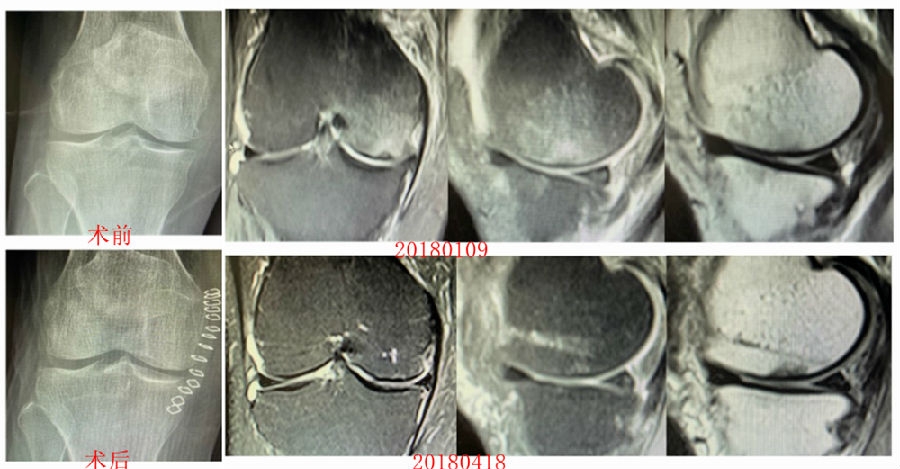

病例1:女,65岁,主诉右膝关节内侧疼痛1周。2018年1月X光未见右膝骨质异常,MR检查见股骨内侧髁骨坏死,半月板相对突出百分比(RPE)28.99%,关节线会聚角1.4°。

予切开行克氏针钻孔减压,口服消炎止痛药物、钙剂及骨化三醇,不负重6周,后改部分负重至3个月。2018年4月复查MR见骨髓水肿基本完全吸收,坏死区局限并修复良好,半月板相对突出百分比(RPE)32.08%,患者临床症状消失。